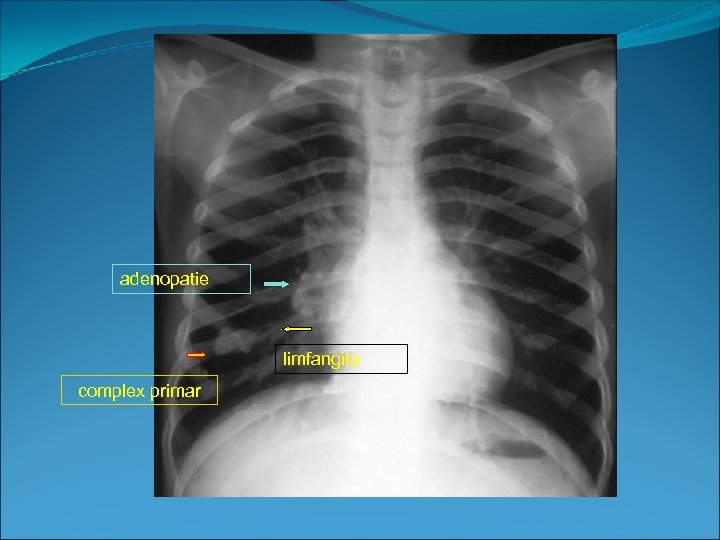

Complex primar Ranke 1. sancrul de inoculare 2. limfangita 3. adenopatii localizate hilar sau paratraheal

1. sancru de inoculare -mic focar de alveolita TB Rx: • opacitate nodulara localizata bazal subpleural cel frecvent pe dreapta) • de obicei izolata • contur flou mai

2. Adenopatie homolaterala -hilara, interbronsica sau latero-traheala, de forma rotunjita sau cu aspect policiclic, rar voluminoasa cu aspect pseudotumoral CT: examinarea computer-tomografica cu substanta de contrast evidentiaza prezenta adenopatiilor, localizarea si necroza de cazeificare, centrala 3. Limfangita -are traducere radiologica doar daca se fibrozeaza si atunci aspectul este de opacitati liniare fine hilipete ce leaga afectul primar de hil

adenopatie limfangita complex primar